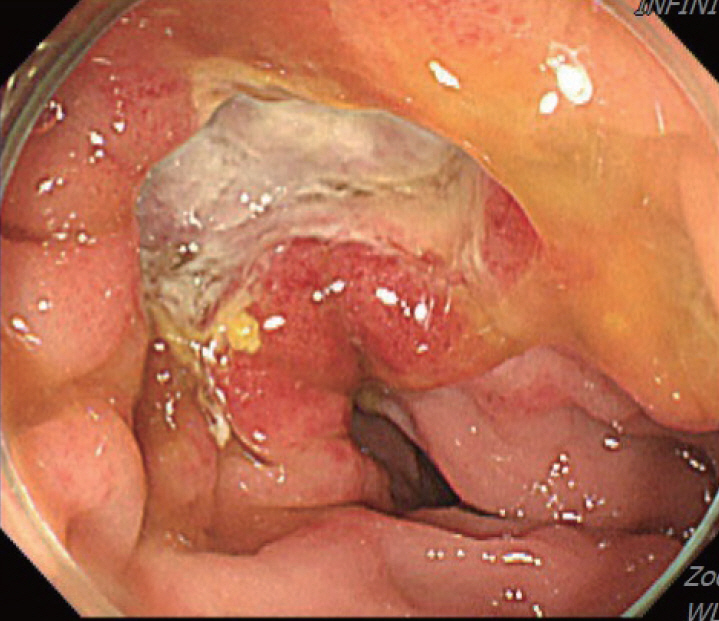

Figure 3.

Colonoscopy showing a scarred sigmoid ulcer 30 cm from the anal verge, with apparent improvement compared to previous findings.

A 70-year-old male underwent sigmoidoscopy after a routine computed tomography (CT) examination, which showed thickening of the sigmoid wall (Fig. 1). Sigmoidoscopy revealed a colonic ulcer, and a biopsy was performed. The lesion was identified as a tubular adenoma; therefore, the patient was referred to the gastroenterology department for repeat biopsy and additional tests. The patient’s medical history included high blood pressure and alcoholic hepatitis. His social history showed that he drank 0.5-1.0 bottle of soju daily and was never a smoker. Information regarding his family history was excluded from the study. The patient had no gastrointestinal symptoms such as abdominal pain or diarrhea, and physical examination findings were unremarkable. Although the biopsy showed a tubular adenoma, the initial colonoscopy indicated that the gross margin of the ulcer was irregularly shaped (Fig. 2), raising suspicion for malignancy. Therefore, despite being asymptomatic, the patient was informed, and another colonoscopy was performed 2 months later. The follow-up examination revealed a scarred sigmoid ulcer located 30 cm from the anal verge, which seemed to have improved compared with the previous findings. Re-biopsy demonstrated features consistent with a simple ulcer (Fig. 3). Accordingly, we concluded that this was a benign colonic ulcer with an inflammatory and ischemic cause rather than cancer, and a follow-up CT scan was sche-duled 1 month later. At the follow-up visit 1 month later, the patient complained of abdominal discomfort after eating for a week, which had not occurred before. He denied having fever, chills, nausea, or vomiting. A subsequent abdominal CT scan showed an approximately 9-cm cavitary lesion abutting the sigmoid colon and urinary bladder dome in the small intestine (Fig. 4). This was accompanied by diffuse nodular omentomesenteric infiltration and peritoneal thickening with small ascites. Based on these findings, the patient was suspected to have a malignant tumor, such as scirrhous carcinoma, inflammatory bowel disease, peritoneal carcinomatosis, or peritonitis, and was referred to a surgeon for surgical treatment. The patient was hospitalized immediately. On admission, the patient complained of abdominal discomfort after eating, and mild generalized abdominal tenderness was noted on physical examination. He was hemodynamically stable. Laboratory testing revealed high white blood cell count of 11.45 × 103/μL (normal range, 4.0-10.0 × 103/μL) with a differential of 67.6% neutrophils (normal range, 38.0-75.0), normal hemoglobin of 16.1 g/dL (normal range, 13.0-17.0), normal platelet count of 151 × 103/μL (normal range, 150-400 × 103/μL), and slightly elevated C-reactive protein level of 7.69 mg/L (normal range, 0.0-5.0). Serum electrolyte and kidney function test results were normal. On the 3rd day of hospitalization, the patient underwent laparoscopic small bowel resection. Immunohistochemical analysis of the resected tissue showed positive staining for CD3, CD4, CD8, CD56, and CAM 5.2 (epithelial marker), and a negative staining for CD10, CD20, CD21, and CD30 (Fig. 5). Histopathological evaluation revealed infiltration by small- to medium-sized T-cell with prominent epitheliotropism, consistent with MEITL. The final diagnosis was MEITL, involving the sigmoid colon, urinary bladder, and peritoneum. Postoperatively, the patient developed persistent ileus with progressive ab-dominal distension and loss of bowel passage, necessitating a second emergency surgery on the 20th day of hospitalization. On the 25th day of hospitalization, the Hemovac drainage became purulent, blood pressure decreased, and the patient went into shock; therefore, a third emergency surgery was performed under the suspicion of bowel perforation. On the 45th day of hospitalization, the patient died of refractory septic shock, presumed to be a complication of intestinal perforation.

MEITL manifests as a wide variety of gastrointestinal symptoms, ranging from abdominal pain, weight loss, and diarrhea to serious symptoms such as bleeding, perforation, and obstruction; however, no characteristic clinical symptoms have been established for this disease [6]. Only 10% of affected patients are diagnosed endoscopically, with majority diagnosed through surgery [7]. As in the present case, MEITL is often discovered accidentally without symptoms or is diagnosed when the disease has already progressed [4]. Among few papers presenting the endoscopic findings of MEITL, Tian et al [8]. described this disease as a semicircular shallow ulcer accompanied by numerous fine granules and mucosal thickening. In our patient, ulceration with associated mucosal thickening was also observed. Histomorphologically, neoplastic cells in MEITL are described as small- to medium-sized, monomorphic, and epitheliotropic lymphocytes, with pale cytoplasm and round nuclei [2]. The cells are CD3+, CD4-, CD5-, CD8+, CD56+, CD30-, MATK+, EBER-, and T-cell receptor-gamma delta+ [9]. Cytotoxic markers such as TIA-1, granzyme B, and perforin are also present [9]. Cyclophosphamide-adriamycin-vincristine-prednisone-based chemotherapy, with or without consolidative autologous stem cell transplantation, remains the mainstay of treatment [3]. In an Asian MEITL series, 72% of patients were treated with chemotherapy, whereas 58% underwent both surgery and chemotherapy [5]. However, the high rate of treatment discontinuation owing to disease progression or treatment-related adverse events continues to be a major concern in this patient population [1]. Surgical resection is necessary when symptoms appear, and approximately 50% of patients undergo emergency surgery for intestinal perforation or obstruction [5,7]. If intestinal perforation occurs, the prognosis is expected to be worse, as chemotherapy is delayed owing to peritonitis, septic shock, and multiple organ failure [10]. In the present case, treatment was likely delayed because of intestinal obstruction prior to anticancer therapy, leading to rapid clinical deterioration. Generally, the diagnostic ratio of intestinal T-cell lymphoma (ITCL) by endoscopy, including tissue biopsy, is low [11] for the following reasons: 1) tissue specimens from endoscopic biopsy are usually not sufficiently large to allow a correct diagnosis; 2) ITCL is primarily located in the submucosa and smooth muscle, and detection of the lesion through the mucosal layer from biopsy specimens is difficult; and 3) the disease can easily be overlooked because of its rarity. Therefore, tissue biopsies of ulcerative gastrointestinal lesions should be performed carefully from the base of the ulcer while considering the possibility of malignant lymphoma [11]. In this patient, despite a prompt biopsy following the incidental detection of a colonic ulcer and a second endoscopic biopsy performed shortly thereafter, an endoscopic diagnosis could not be achieved. If several deeper biopsies, including those of the submucosa, were performed at the time of the initial endoscopy, the possibility of early diagnosis may have increased. Moreover, although our patient underwent colonoscopy over a short follow-up period, the ulcer showed an atypical clinical course, appearing to improve and form a scar within a short interval. Such a presentation has rarely been reported in the related literature, and we report this case to highlight its unusual endoscopic features. Additionally, owing to this atypical pattern, careful differen-tiation from other diseases, such as benign ulcers or inflammatory bowel disease, is necessary. Our case underscores the importance of early diagnosis of MEITL, as the rapid progression of the disease can have a fatal consequence. Endoscopists and clinicians need to be vigilant in understanding endoscopic and histological findings to ensure prompt diagnosis and treatment of this aggressive disease.